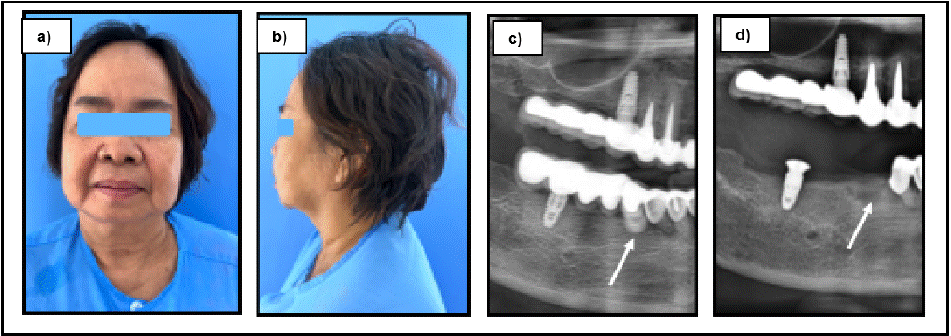

On day seven, a follow-up CT scan was done. The subcutaneous emphysema was almost resolved dramatically, with only minimal residual air was remained. The retained implant fragment was performed under local anesthesia without complication. The patient continued to recover and was discharged on day nine with instructions for outpatient follow-up until complete clinical and radiographic resolution of the subcutaneous emphysema (Figure 4).

Figure 4: a) and b) clinical extraoral photographs were obtained on postoperative day 7 follow-up, illustrating significant resolution of cervicofacial edema with

only slightly residual swelling. a) and b) pre and postoperative OPGs were demonstrated the removal of remain implant and prosthesis.